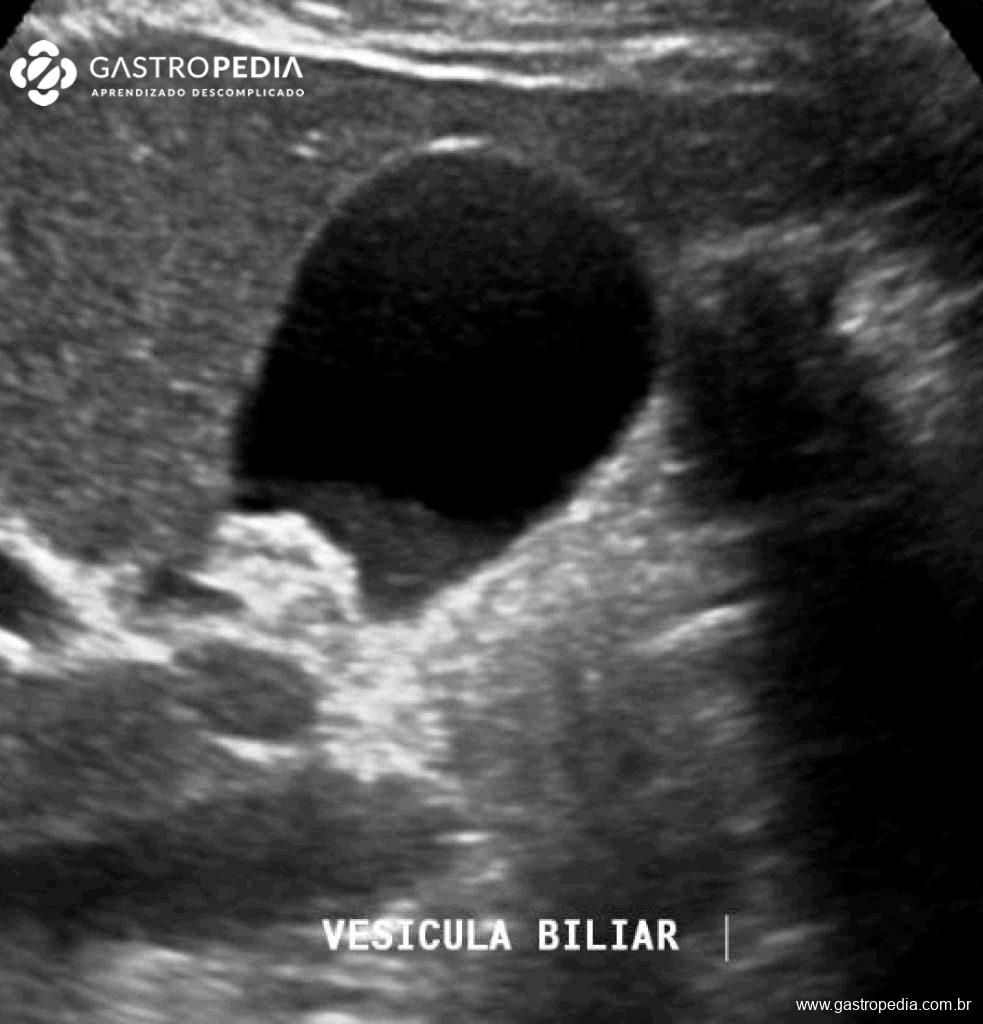

Descrito principalmente como um achado ultrassonográfico, a vesícula biliar apresenta um conteúdo hipoecogênico que se deposita formando nível em relação a bile mais fluída e sem formar sombra acústica posterior. O barro biliar muda de posição lentamente de acordo com o decúbito do paciente.